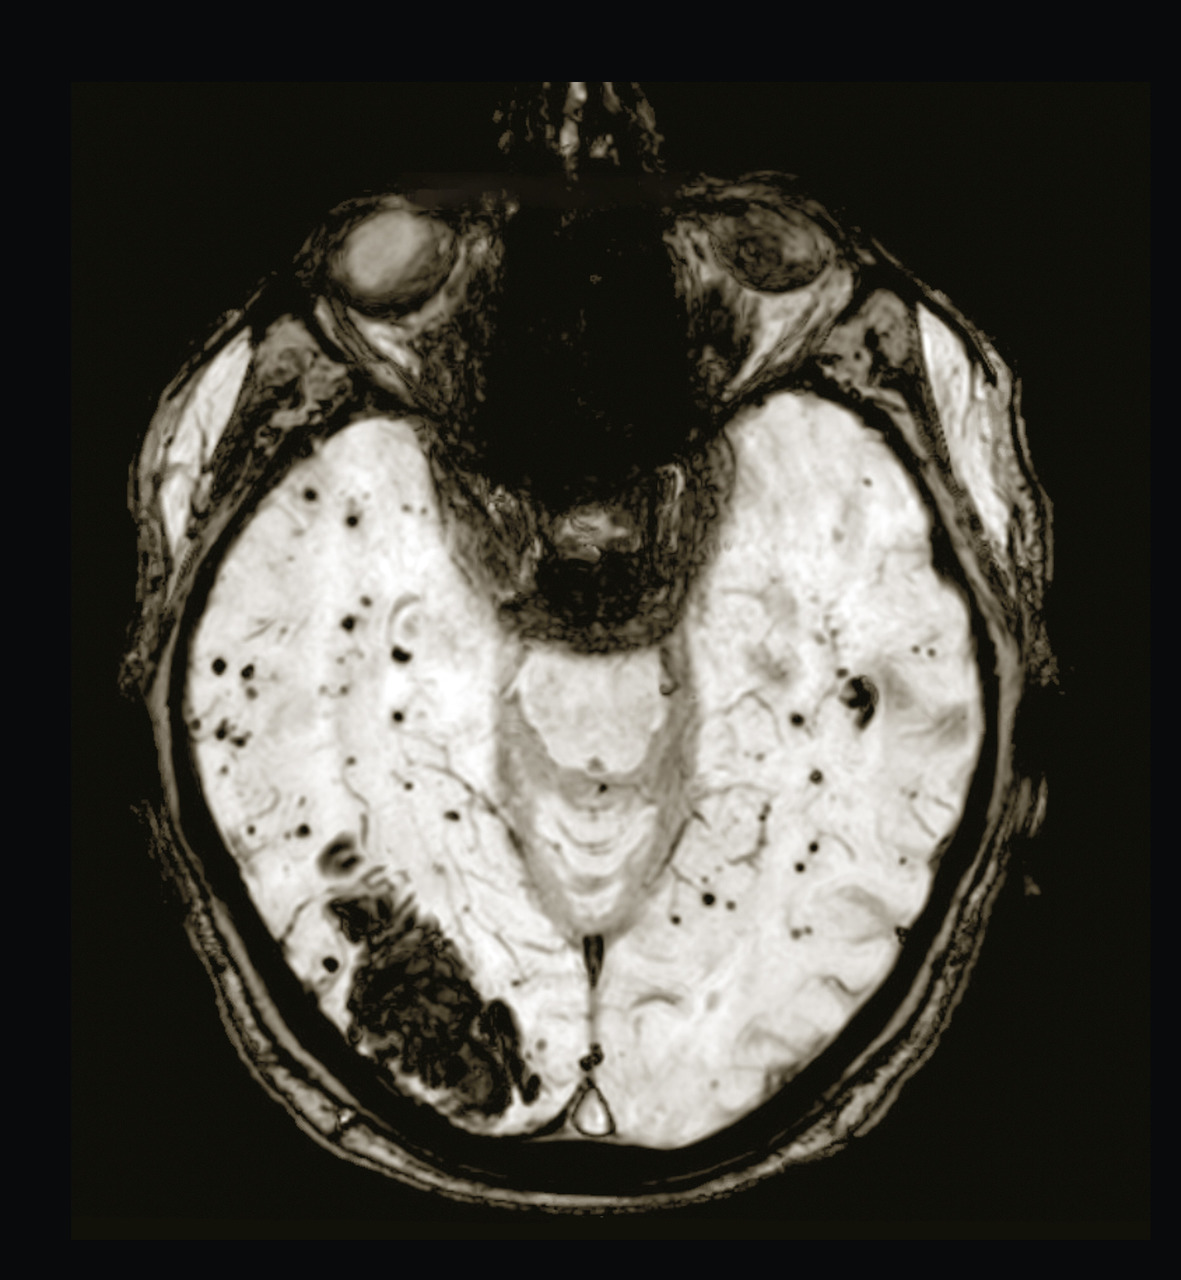

Les hémorragies intracérébrales spontanées résultent d’un saignement cérébral intraparenchymateux en lien avec la rupture de petits vaisseaux généralement touchés par une microangiopathie sporadique. Elles représentent environ 15 % des accidents vasculaires cérébraux (AVC) dans les pays occidentaux. Les hémorragies localisées dans les régions profondes du cerveau sont le résultat de la rupture des petites artérioles touchant préférentiellement le putamen et le thalamus et sont sous-tendues par la microangiopathie des perforantes longues favorisée par les facteurs de risque vasculaires (fig. 1A et B ). Les hémorragies de localisation lobaire proviennent de la rupture d’artérioles de petite et moyenne taille perforant le cortex et la substance blanche sous-corticale et sont principalement sous-tendues chez le sujet âgé par l’angiopathie amyloïde cérébrale (fig. 2 ).

Les séquences d’imagerie par résonance magnétique (IRM) dites sensibles au sang écho de gradient T2* ou SWI (susceptibility weighted imaging) permettent d’identifier l’hémorragie cérébrale à la phase aiguë et donnent de plus des informations sur le parenchyme cérébral autour de l’hémorragie. Quand l’IRM n’est pas réalisable (indisponibilité ou contre-indication), la tomodensitométrie s’avère aussi sensible que l’IRM à la phase aiguë, mais sa sensibilité décroît avec le temps, notamment pour les hémorragies de petite taille. Les hémorragies cérébrales spontanées (angiopathie amyloïde cérébrale et maladie des petites artères) représenteraient environ 80 % des hémorragies cérébrales non traumatiques. Néanmoins, il convient de rechercher devant certains signes cliniques ou radiologiques d’autres causes relevant de prises en charge spécifiques (v . tableau ).1, 2